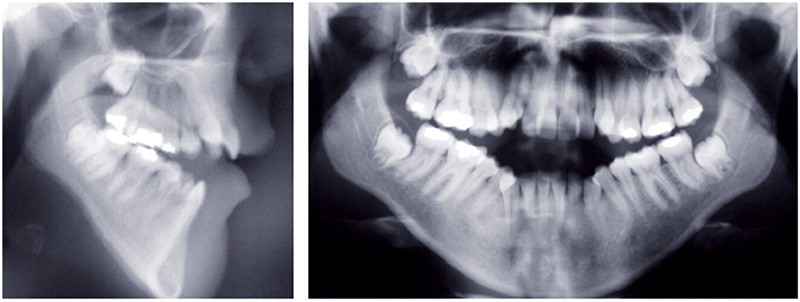

Au niveau squelettique, elle présente une classe I associée à une endognathie maxillaire et une hyperdivergence mandibulaire majeure liée à un excès de croissance alvéolaire verticale postérieure maxillaire et une inclinaison mandibulaire très marquée (fig. 1 et 3).

Sur le plan occlusal et dentaire, on observe une classe I molaire, une occlusion transversale en bout à bout à droite et inversée à gauche et une béance antérieure sévère s’étendant jusqu’aux molaires. Un encombrement est présent aux deux arcades avec des dystopies canines importantes (fig. 2).